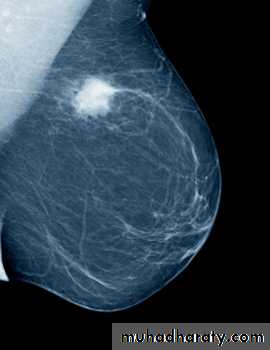

Benign calcification

Malignant microcalcification